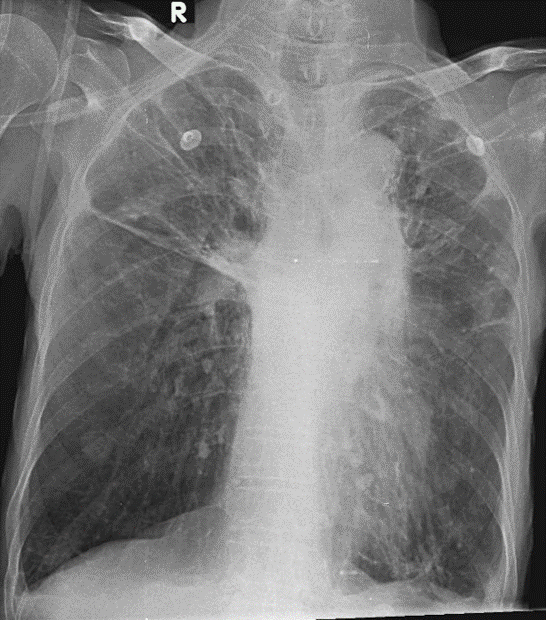

1-Xơ rải rác hai phổi 2-Khí phế thũng rải rác hai phổi đáy > đỉnh 3-Dày dính màng phổi hai bên 4-Tràn dịch màng phổi hai bên lượng ít 5-Cung động mạch chủ đóng vôi